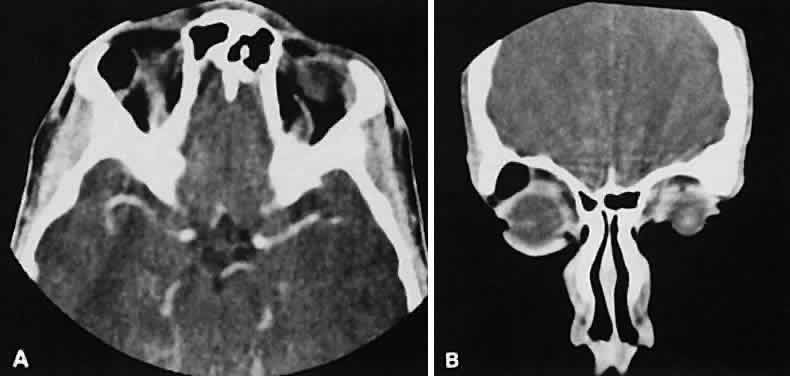

Graves' orbitopathy probably represents the most frequent cause of proptosis and EOM enlargement. The CT findings are fairly stereotyped and typically display various degrees of EOM enlargement (Fig. 7). The inferior rectus muscle usually is affected earliest, followed by the medial rectus, superior rectus, and finally the lateral rectus muscle. Rootman and colleagues13 noted more frequent involvement of the superior rectus/levator and medial rectus muscles than what had been reported previously with Graves' orbitopathy. These muscles can be affected in isolation, with the exception of the lateral rectus. To the best of our knowledge, isolated lateral rectus enlargement has not been reported in Graves' orbitopathy and in our experience usually is associated with a sphenoid wing meningioma.

Fig. 7. Graves' orbitopathy with two variations. Axial (A) and coronal (B) views show symmetric fusiform enlargement of the extraocular muscles with tapered muscle insertions. Note the predominant enlargement of the inferior, medial, and superior rectus muscles with lesser involvement of the lateral rectus muscle, a frequent pattern of enlargement in Graves' orbitopathy. Axial (C) and coronal (D) views of Graves' orbitopathy with expansion of retrobulbar ground substance and relative sparing of the extraocular muscles.